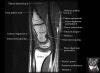

손목 관절의 MRI 단면 영상

- Sagittal section

Sagittal T1 evaluates the tendons, bone marrow and relationships between the osseous structures.